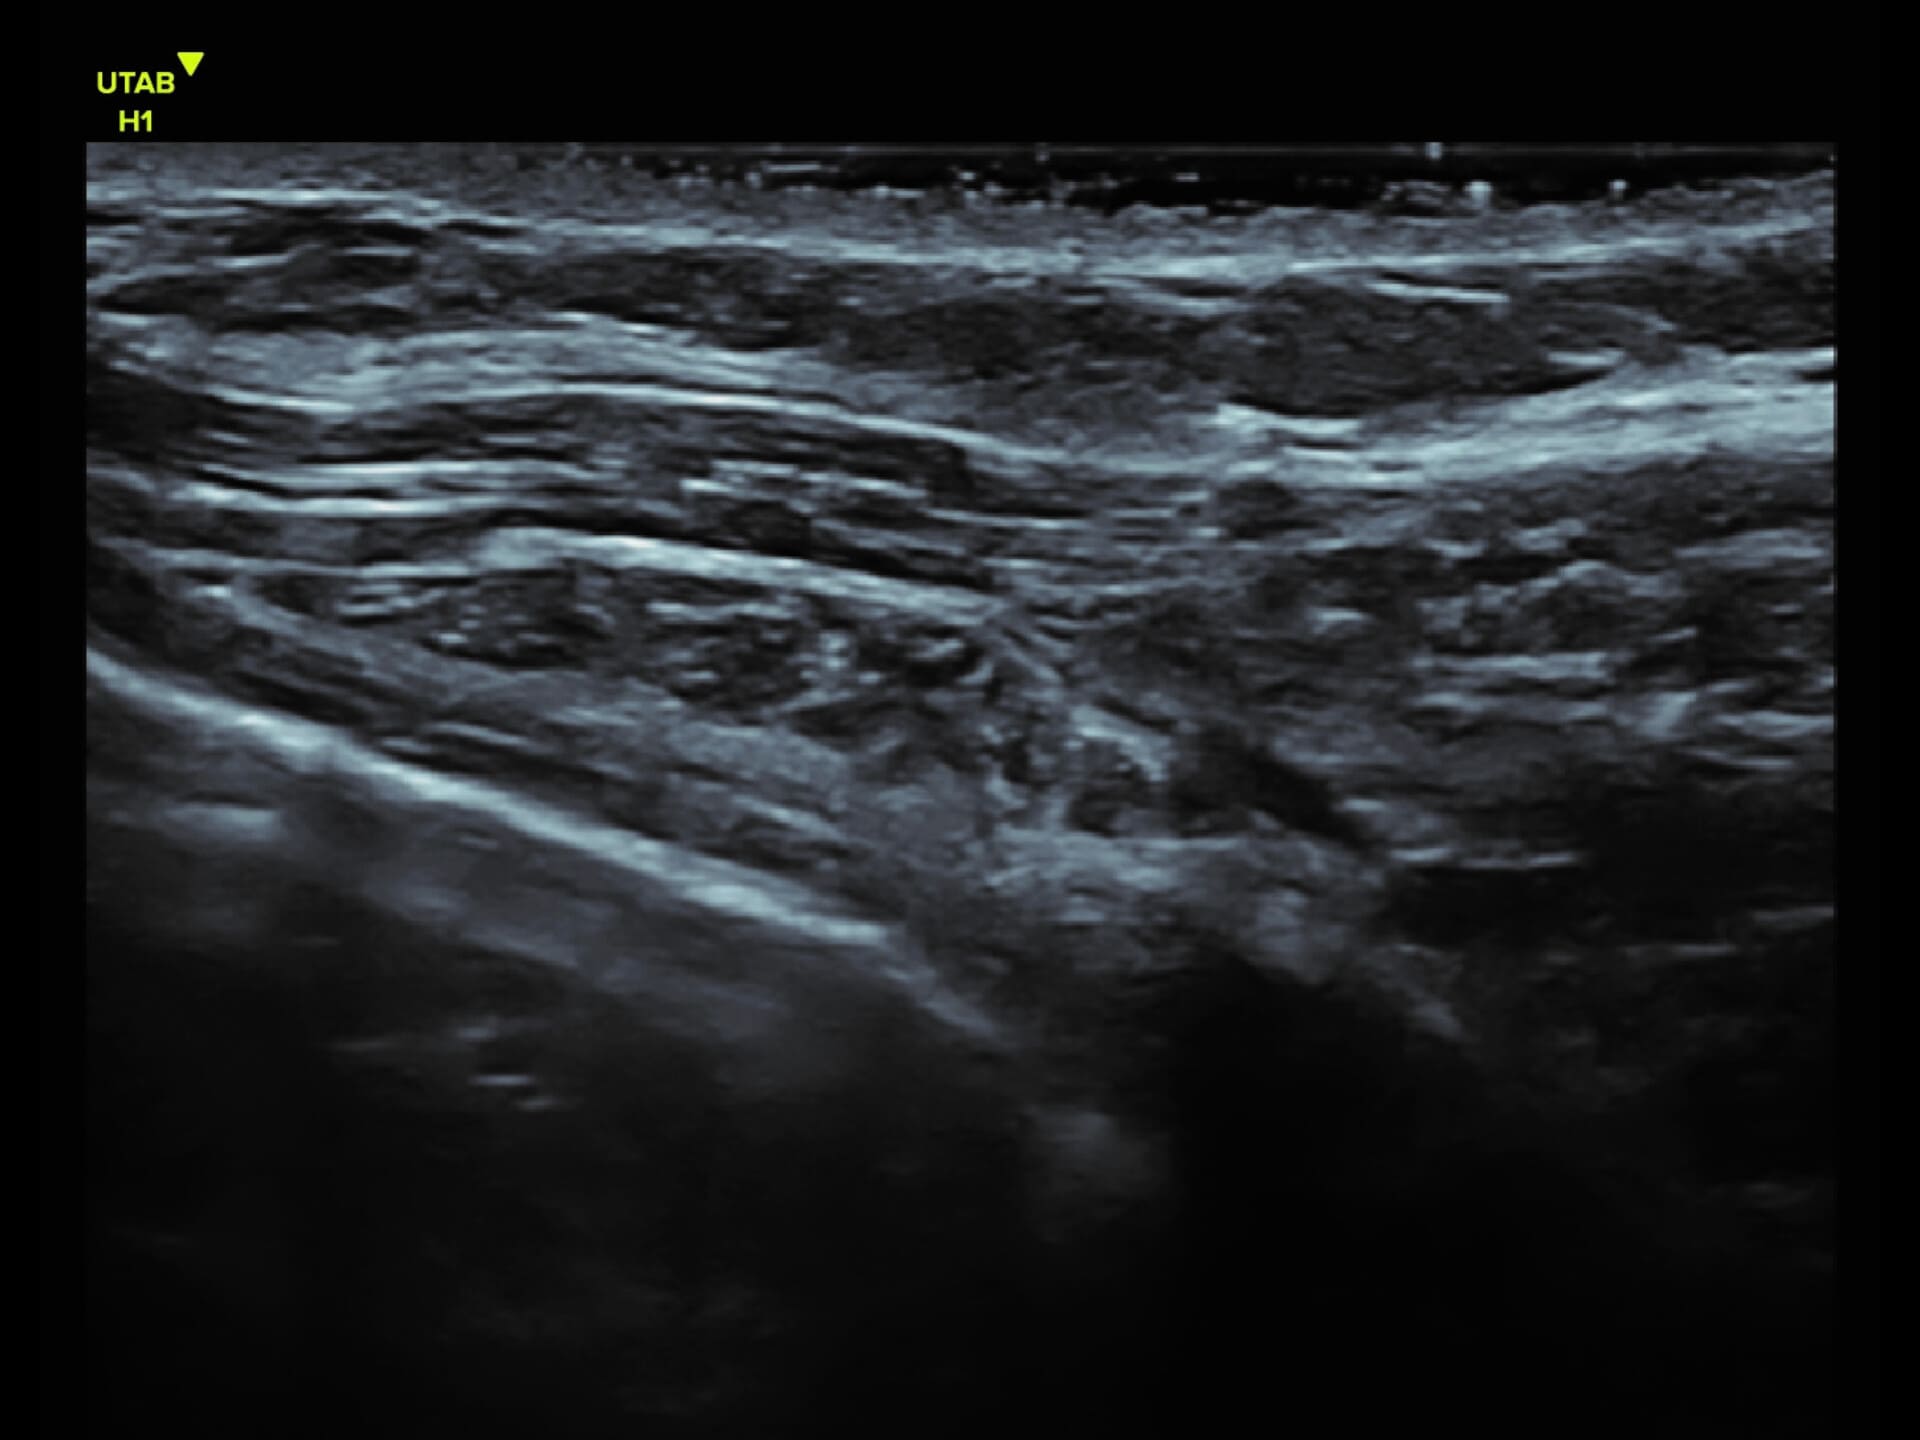

L9-2 Linear Array Probe

Precision at the Surface

Crystal-clear imaging for muscles, vessels, and soft tissues—perfect for targeted exams and real-time procedures.

The L9 – 2 is a linear array ultrasound probe featuring advanced wideband technology, which enables a broader frequency range for superior image resolution and clarity. This enhanced imaging capability makes it ideal for a range of clinical applications.

About L9-2

The L9 – 2 is a linear array ultrasound probe featuring advanced wideband technology, which enables a broader frequency range for superior image resolution and clarity.

This enhanced imaging capability makes it ideal for a range of clinical applications.

L9 - 2 Linear Array Probe

2 - 10 MHz

DLP

192 elements

Applications:

Musculoskeletal, Thyroid, Small Parts, Pediatrics, Peripheral Vascular, Breast, Obstetrics

B-mode, HI, XBeam, Speckle Reduction, Virtual Convex, M-mode, PW (Update, Duplex, Triplex, HPRF), CFM, PD

7 x 43 mm